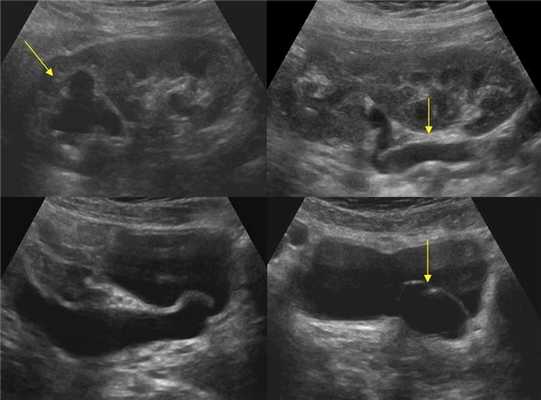

Рисунок. На УЗИ расширенный дистальный отдел мочеточника (1, 2, 3). Про уретероцеле (3) подробнее смотри здесь.

Рисунок. Пациент с острой почечной коликой. На УЗИ слева в дистальном отделе мочеточника гиперэхогенное округлое образование с акустической тенью (1), мочеточник расширен на всем протяжении (2), лоханка и большие чашечки умеренно расширены (3, 4). Заключение: Камень в дистальном отделе мочеточника. Вторичный мегоуретер и гидронефроз 2 степени.